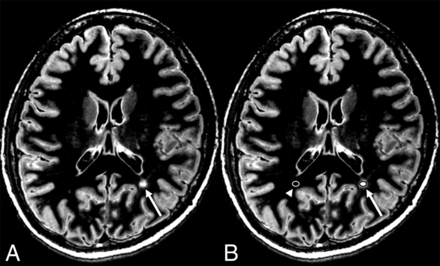

ROI analyses were performed on synthetic and conventional DIR images by a single investigator (M.N.) blinded to the clinical information. For the quantitative analysis, the signal intensities of the MS lesions and corresponding WM were measured by ROI analyses and their mean values were recorded. A circular ROI that covered almost the entire lesion was placed on each MS plaque that measured ≥5 mm in diameter. The ROI was then copied and pasted on the corresponding WM (Fig 3). For a supratentorial lesion, the corresponding WM was defined as the normal-appearing WM contralateral to that lesion. For an infratentorial lesion, it was defined as the normal-appearing WM in the brain stem in the same section.

An example of ROI placement. A plaque (arrow) is shown on the synthetic DIR image (A). A circular ROI (arrow) that covers almost the entire lesion is placed in B. The ROI was copied and pasted on the contralateral normal-appearing WM (arrowhead).

The lesion-to-WM contrast was defined as the difference between the mean SI of a lesion and that of the corresponding WM divided by the SI of the corresponding WM. The lesion-to-WM CNR was defined as the difference between the SI of a lesion and that of the corresponding WM divided by the noise of each sequence. The GM-to-WM and GM-to-CSF contrasts and CNRs were calculated likewise.